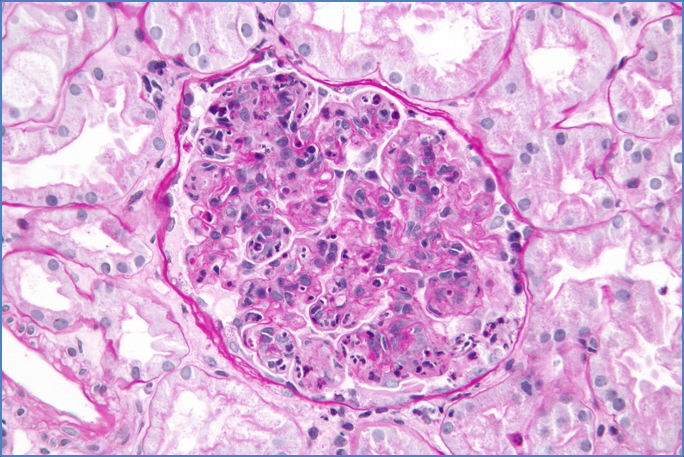

- Renal biopsy (if atypical or in adults):

- Glomerular hypercellularity with neutrophilic infiltrate

- Subepithelial immune complex deposits (often “hump”-shaped on EM)